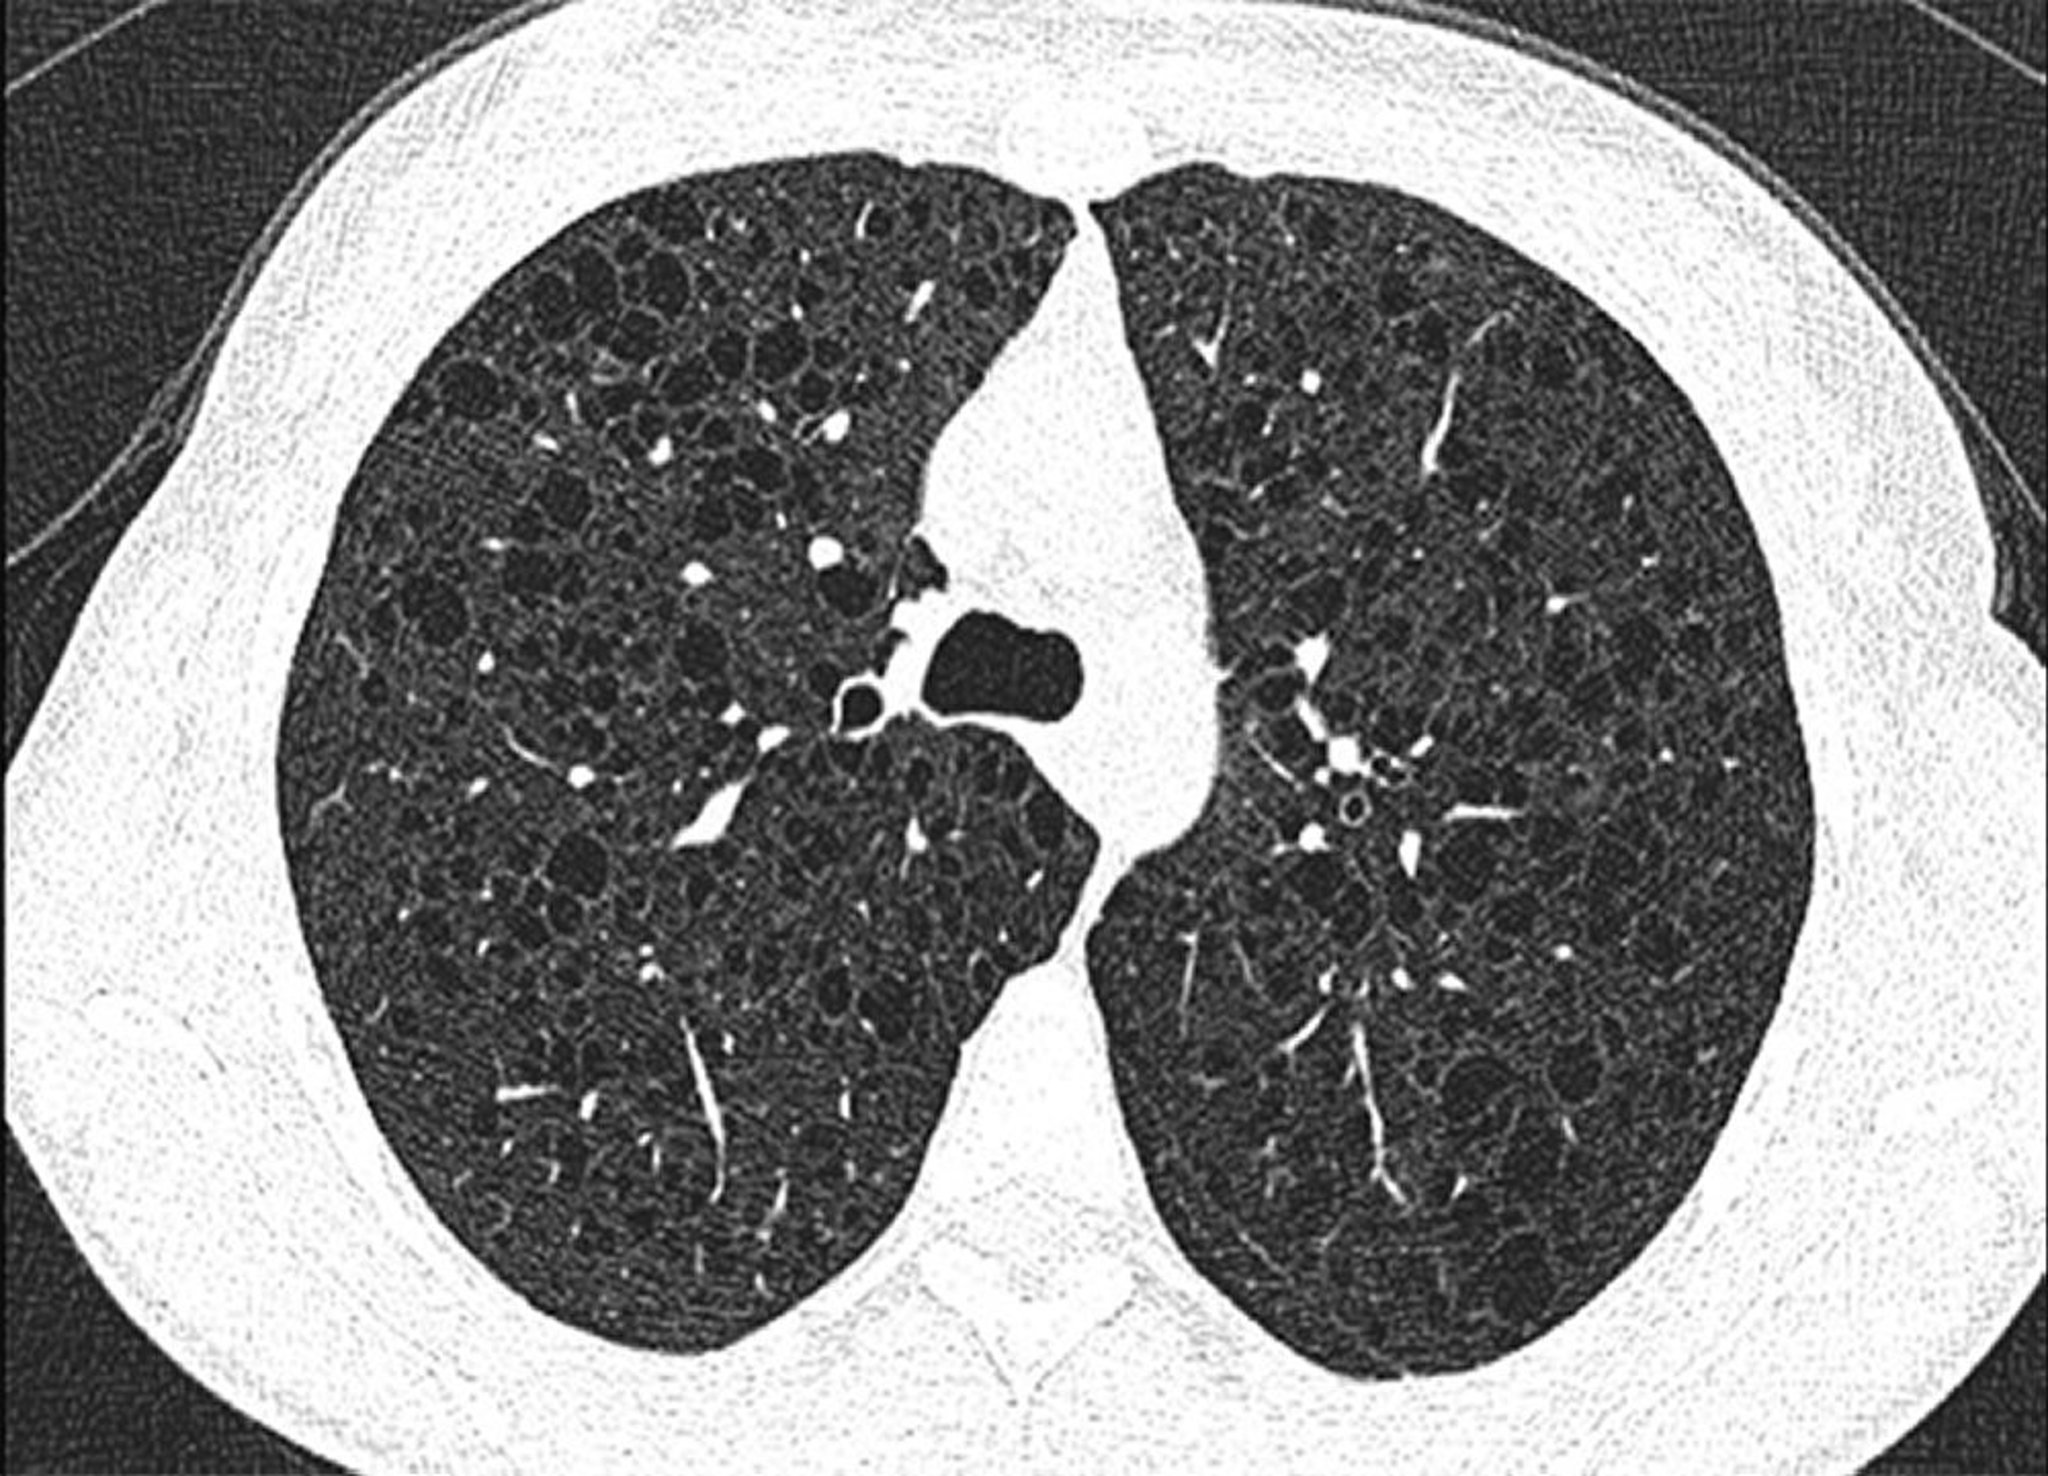

Eine HRCT wird bei allen Patienten mit Verdacht auf die Erkrankung empfohlen; Der Nachweis mehrerer kleiner, diffus verteilter, dünnwandiger Zysten ist in der Regel pathognomonisch für LAM. Pneumothorax, Pleuraergüsse und chylöse Ergüsse (im Thorax oder Abdomen) können in der Bildgebung sichtbar sein.

Dieses Bild zeigt diffuse Zysten in beiden Lungen bei einem Patienten mit Lymphangioleiomyomatose.

Image courtesy of Joyce Lee, MD, MAS.